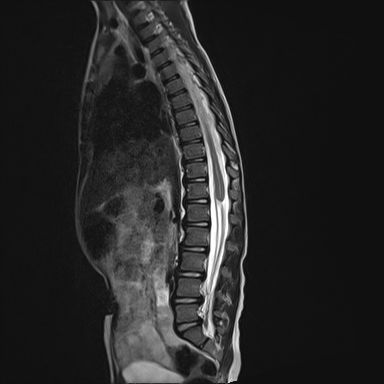

Ankylosing Spondylitis

Chronic inflammatory seronegative spondyloarthropathy primarily affecting the axial skeleton

Anatomy / Structural Changes

Progressive inflammation of:

1- Sacroiliac joints

2- Spine

Leads to:

1- Vertebral body squaring

2- Syndesmophyte formation

3- Progressive spinal rigidity

Characteristic Appearance

1- “Bamboo spine” due to fused vertebrae

2- Loss of normal spinal flexibility

Presentation, Diagnostic Features & Key Findings

Radiographic / Structural

1- Squared vertebral bodies

2- Syndesmophytes

3- “Bamboo spine”

4- Bilateral sacroiliitis